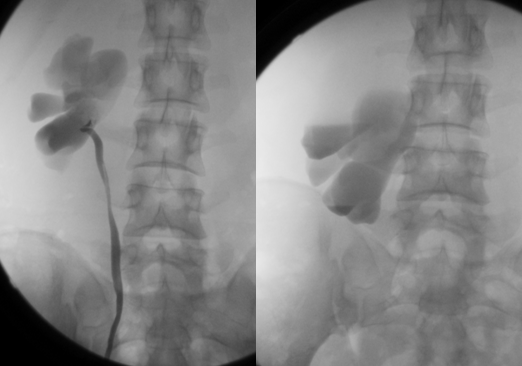

腔静脉后输尿管

腔静脉后输尿管因胚胎期下腔静脉发育异常所导致的输尿管位置、走行等方面的改变,而不是原发于输尿管本身的变异

腔静脉压迫可引起流尿流不畅,导致肾盂积水

其具体走行方向为:离肾盂后先向下向内、由脊柱与下腔静脉之间通过,再从后面绕过下腔静脉、由主动脉与下腔静脉之间穿过,再向下行从正常路线进入膀胱

IVP 可见肾盂、肾盏及上部输尿管积水扩张,输尿管向中线弯曲,在相当于腰 3-4 水平与脊柱影重叠并变细,侧位见此部位输尿管被推压紧贴于椎体前缘,整个输尿管迂曲变形,呈镰刀状、S 状或鱼钩状